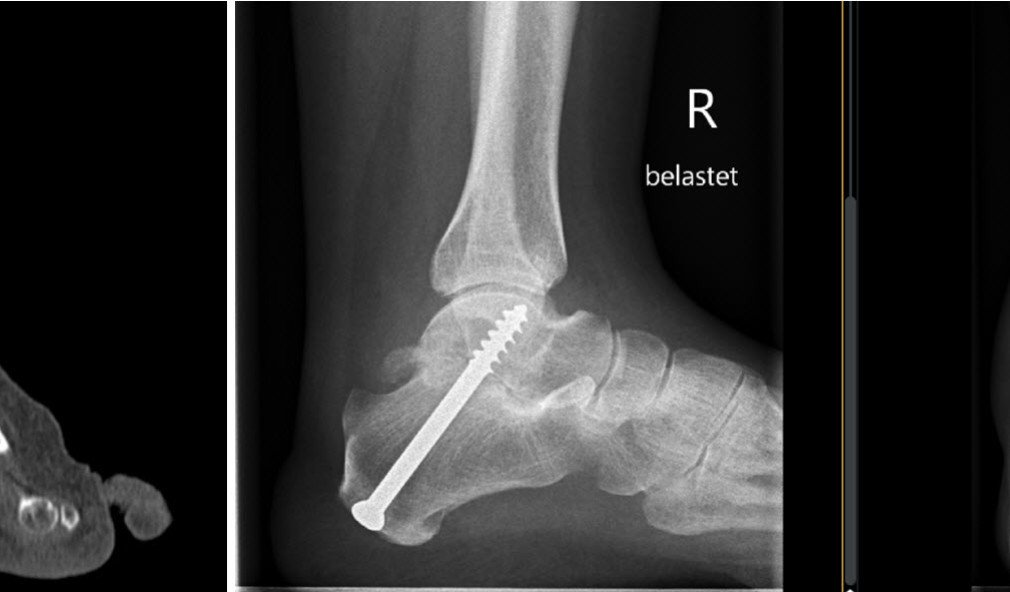

Fall des Monats – Arthrose im unteren Sprunggelenk

Eine 33-jährige Verkäuferin stellt sich im Rahmen unserer Sprechstunde mit belastungsabhängigen Rückfussschmerzen vor. Diese bestünden seit sie sich bei einem Treppensturz  8 Monate zuvor eine kleine Fraktur des Fersenbeins zugezogen habe. In der mitgebrachten MRI-Untersuchung sieht man degenerative Veränderungen des unteren Sprunggelenkes, welches sich zwischen Sprungbein und genanntem Fersenbein befindet.